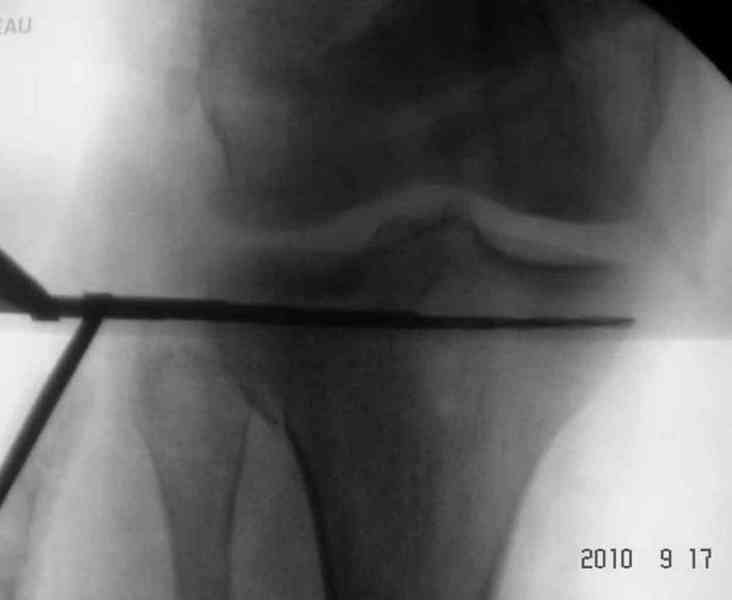

Re: Перелом голени

В остром периоде для стабилизации перелома подойдет любой дистракционный аппарат "голень-стопа", и больной получит свободу от скелетного вытяжения.

Из нашего опыта при переломах голени с высокой энергией одним из частых осложнении является компартмент синдром, но КС наблюдается при переломах тибиал плато чаще, чем при дистальных переломах голени.

Для внутрисуставных переломов необходимо идеальное сопоставление, а такая задача без КТ срезов усложнится. Только КТ надо делать после дистракции сустава, иначе нельзя получить объективную информацию.

Основная задача в лечении околосуставных переломов является создание солидного базиса в субхондральной зоне. Пластина подпорка (Butress) или субхондральные перкутанные шурупы в виде плота (Raft) для ранних движении.

У больного двухстороннее повреждение, ограничен в нагрузке не менее 8-10 недель. После односторонней фиксации будет активным, хотя бы в пределах койки. Без спешки дождаться улучшения кожных покровов, и аппаратом Илизарова в комбинации с шурупами или спицами, из мини-доступов.